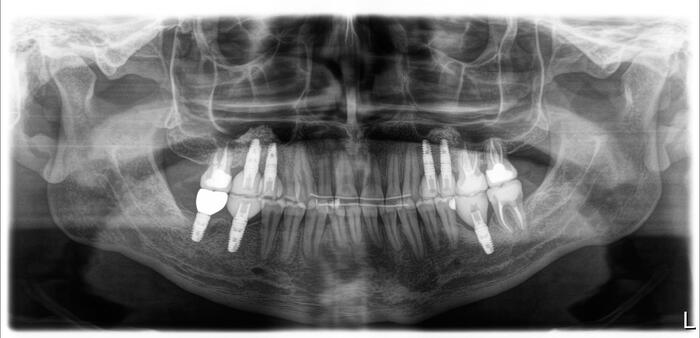

Дабы не перегружать вас обилием одинаковых картинок, я оставлю один рентгеновский снимок, но отмечу, что установка имплантатов на верхней и нижней челюсти проводилась с разницей в 10 дней.

На верхней челюсти было дополнительно удалено два боковых резца с одномоментной установкой имплантатов, так же они были установлены в области четверок и шестых зубов. Дополнительно было проведено наращивание костной ткани - двусторонний синус - лифтинг. О том, что это такое, можно почитать ТУТ и ТУТ.

После нехитрых манипуляций мы прощаемся с Русланом на 4 месяца.

Этого времени достаточно на приживление имплантатов.

Контрольный рентгеновский снимок: